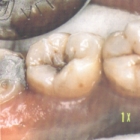

Karies

Bildquelle: Dental World online